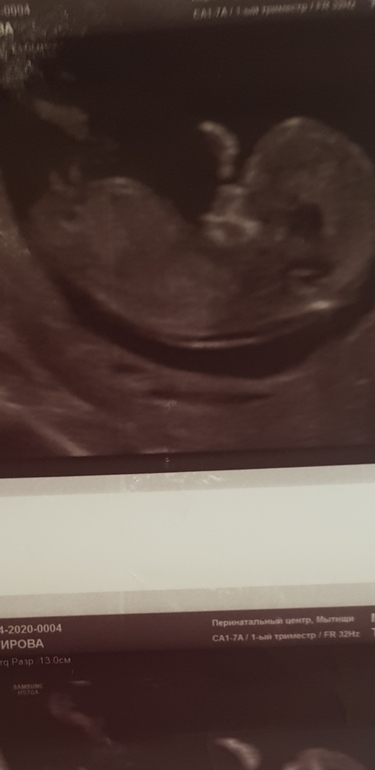

УЗИ 12 недель фото

Кто угадает на каком фото мальчик на каком девочка ?)))

Помогите определить пол пожалуйста 12,4 недель фото узи

Здравствуйте дорогие мамки всем за ранее спасибо ,,,, вот узи 12,4 недель здесь есть опытные мамки у кого как было ,? Как думаете у нас принцесса будет или принц ????🙏🥰